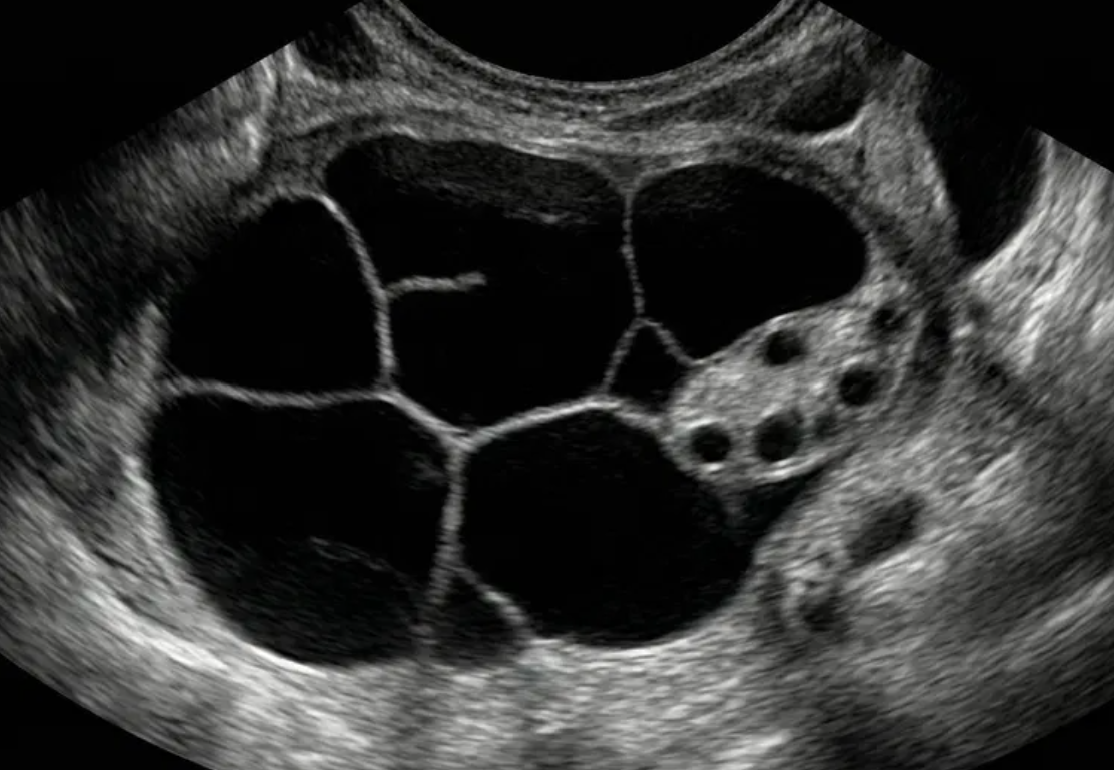

O-RADS US 3 — Baixo Risco de Malignidade

Risco: <10%Cisto unilocular ≥ 10 cm, cistos dermoides/endometriomas/hemorrágicos ≥ 10 cm, cisto unilocular com parede irregular < 3 mm, cisto multilocular < 10 cm com parede lisa, lesão sólida com superfície lisa.

Conduta

Se não removida cirurgicamente, considerar seguimento com US em 6 meses. Se sólido considerar US com especialista (se disponível) ou RM (com classificação O-RADS MRI). Seguimento com ginecologista.